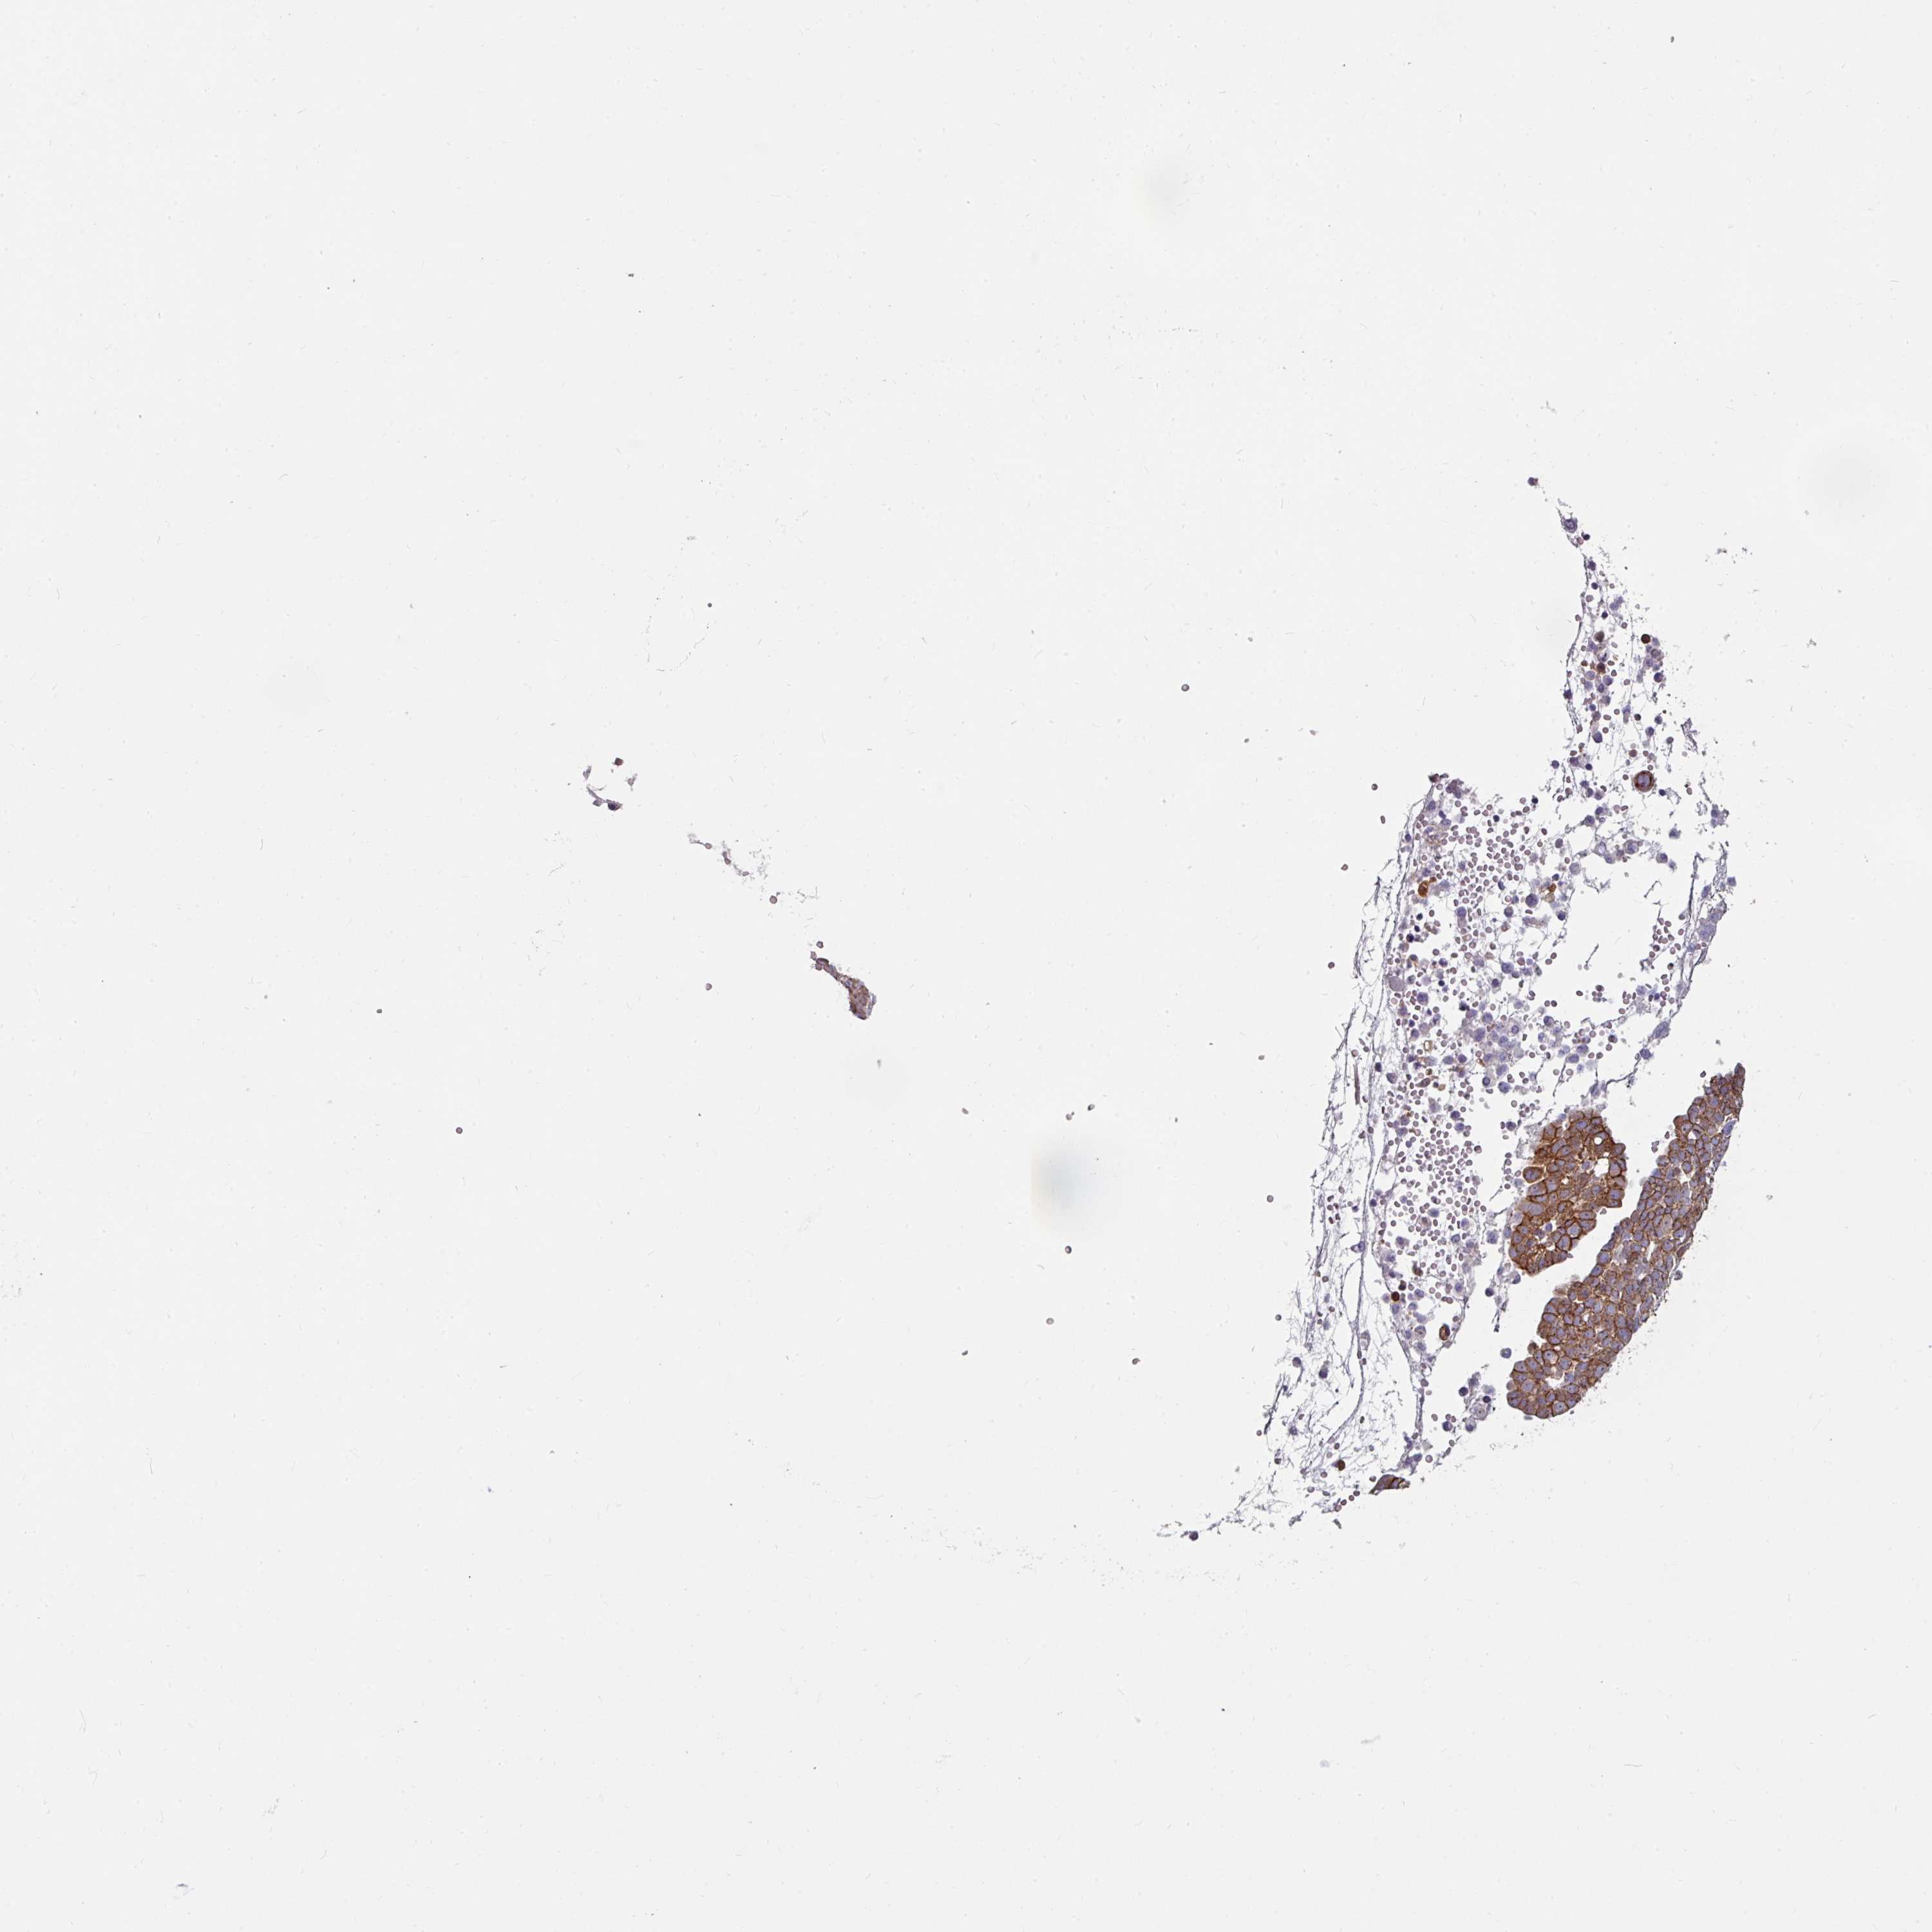

OVARIAN CANCER - Protein expressioni

A mouse-over function shows sample information and annotation data. Click on an image to view it in a full screen mode. Samples can be filtered based on level of antibody staining by selecting one or several of the following categories: high, medium, low and not detected. The assay and annotation is described here.

Note that samples used for immunohistochemistry by the Human Protein Atlas do not correspond to samples in the TCGA dataset.

Antibody stainingi

Antibody staining in the annotated cell types in the current human tissue is reported as not detected, low, medium, or high, based on conventional immunohistochemistry profiling in selected tissues. This score is based on the combination of the staining intensity and fraction of stained cells.

Each image is clickable and will lead to virtual microscopy that enables deeper exploration of all samples and also displays staining intensity scores, fraction scores and subcellular localization as well as patient and tissue information for each sample.

Antibody HPA032047

Antibody CAB002139

Cystadenocarcinoma, serous, NOS

Carcinoma, endometroid

Cystadenocarcinoma, mucinous, NOS

Carcinoma, NOS